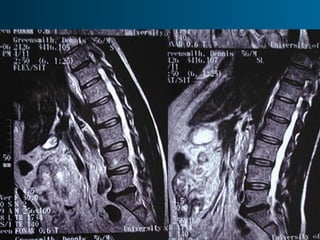

Foraminal

stenosis